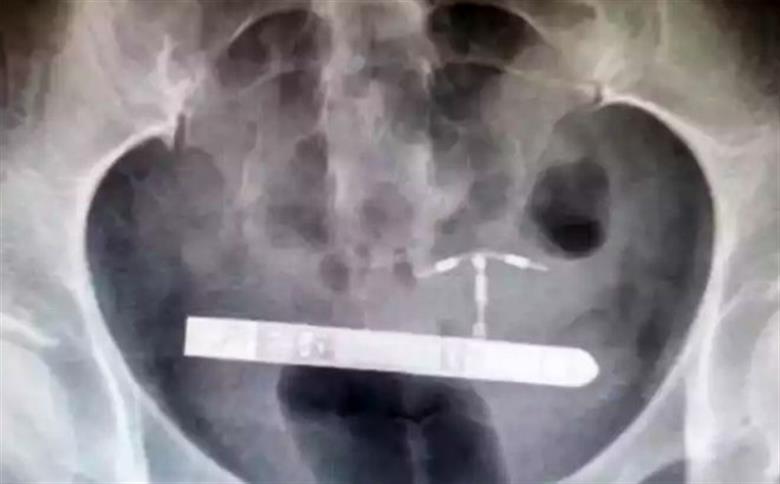

Assustada, a mulher resolveu ir até um hospital. Nos primeiros exames, a equipe médica não localizou o brinquedo sexual dentro da vagina dela. Horas depois, a paciente passou por um raio-X, que indicou que o vibrador estava alojado ao lado da bexiga dela.

Com o diagnóstico, os médicos encaminharam a mulher para a cirurgia. Ela já está totalmente recuperada e, agora, a americana pretende entrar com uma ação na Justiça contra a empresa fabricante do brinquedo sexual. Segundo ela, o ?design pequeno e estreito do vibrador é perigoso?.